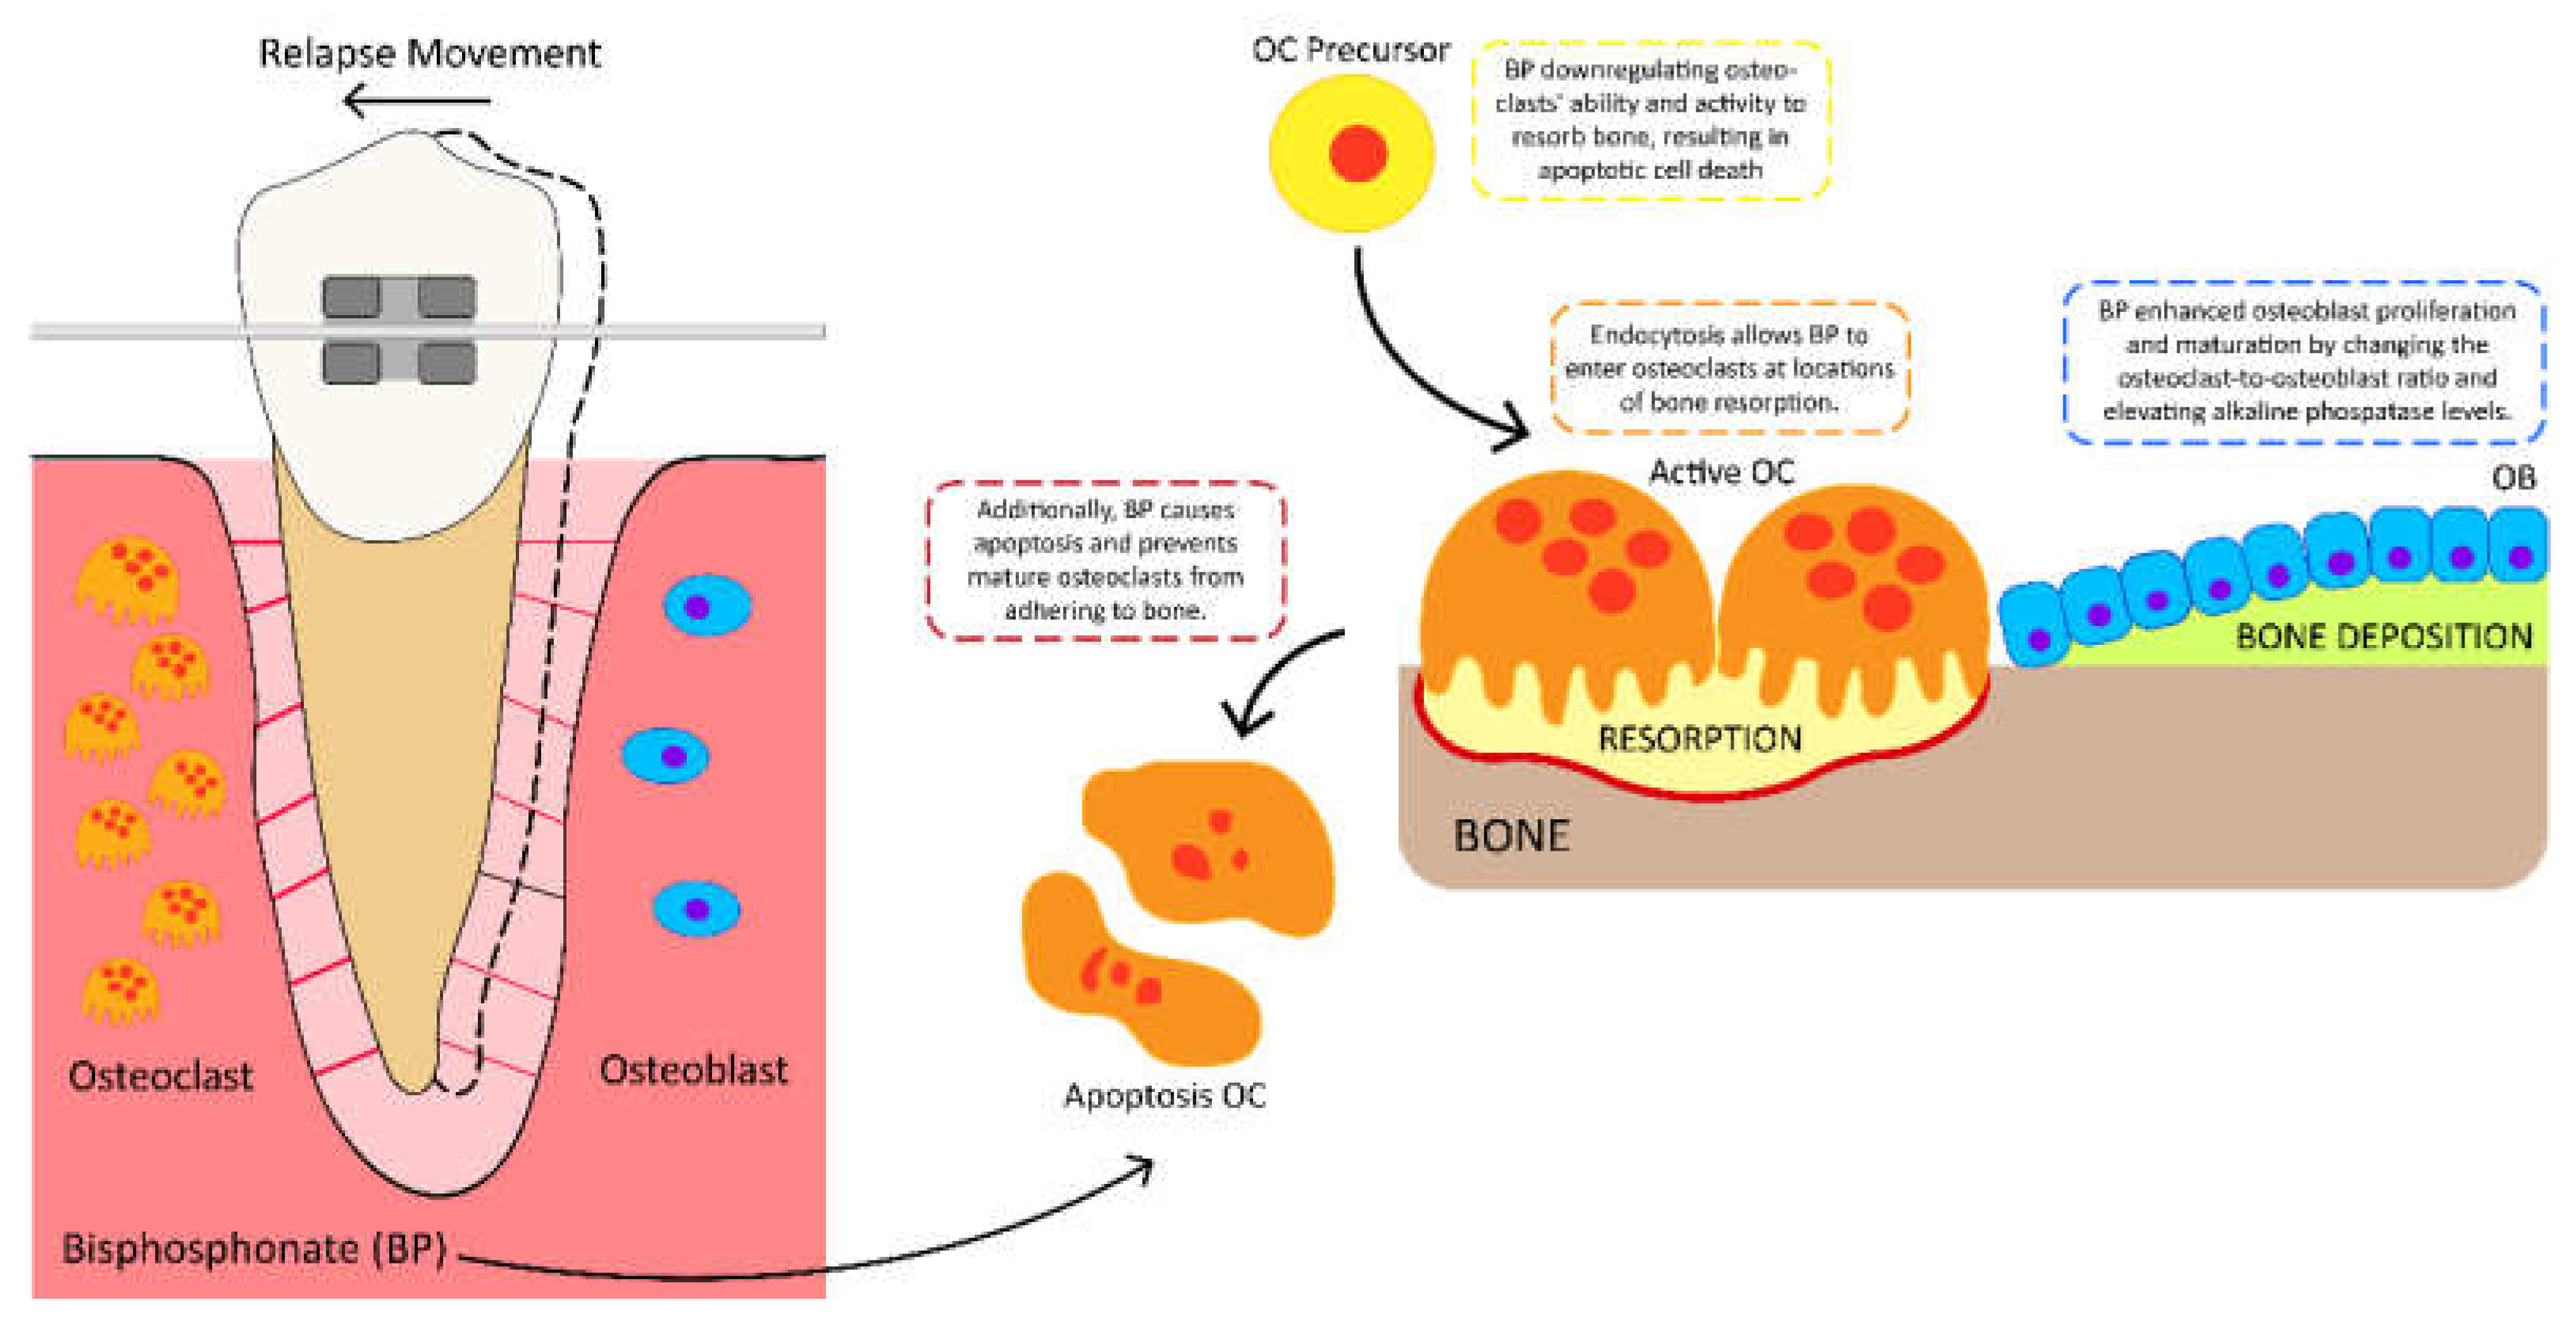

5. The Potential Benefits of Using Bisphosphonate Risedronate Hydrogel to Prevent Orthodontic Relapse Movement

- Frith, J.C.; Mönkkönen, J.; Auriola, S.; Mönkkönen, H.; Rogers, M.J. The molecular mechanism of action of the antiresorptive and antiinflammatory drug clodronate: Evidence for the formation in vivo of a metabolite that inhibits bone resorption and causes osteoclast and macrophage apoptosis. Arthritis Rheum. 2001, 44, 2201–2210. [Google Scholar] [CrossRef]

- Roelofs, A.J.; Thompson, K.; Gordon, S.; Rogers, M.J. Molecular mechanisms of action of bisphosphonates: Current status. Clin. Cancer Res. 2006, 15, 6222s–6230s. [Google Scholar] [CrossRef] [Green Version]

- Rogers, M.J. New insights into the molecular mechanisms of action of bisphosphonates. Curr. Pharm. Des. 2003, 9, 2643–2658. [Google Scholar] [CrossRef]

- Krishnan, S.; Pandian, S.; Kumar, S.A. Effect of bisphosphonates on orthodontic tooth movement-an update. J. Clin. Diagn. Res. 2015, 9, ZE01–ZE05. [Google Scholar] [CrossRef]

- Fujimura, Y.; Kitaura, H.; Yoshimatsu, M.; Eguchi, T.; Kohara, H.; Morita, Y.; Yoshida, N. Influence of bisphosphonates on orthodontic tooth movement in mice. Eur. J. Orthod. 2009, 31, 572–577. [Google Scholar] [CrossRef]

- George, E.L.; Lin, Y.L.; Saunders, M.M. Bisphosphonate-related osteonecrosis of the jaw: A mechanobiology perspective. Bone Rep. 2018, 5, 104–109. [Google Scholar] [CrossRef]

- Adachi, H.; Igarashi, K.; Mitani, H.; Shinoda, H. Effects of topical administration of a bisphosphonate (risedronate) on orthodontic tooth movements in rats. J. Dent. Res. 1994, 73, 1478–1486. [Google Scholar] [CrossRef] [PubMed]

- Goya, J.A.; Paez, H.A.; Mandalunis, P.M. Effect of topical administration of monosodium olpadronate on experimental periodontitis in rats. J. Periodontol. 2006, 77, 1–6. [Google Scholar] [CrossRef] [PubMed]

- Utari, T.R.; Ana, I.D.; Pudyani, P.S.; Asmara, W. The Potential of Bisphosphonate Risedronate Hydrogel in Preventing Relapse Movement. Cumhur. Dent. J. 2022, 25, 103–110. [Google Scholar] [CrossRef]

- Utari, T.R.; Kurniawan, M.F.; Andewa, S.M. The controlled release profile of risedronate emulgel to inhibit relapse movement in orthodontic treatment. Padjajaran J. Dent. 2022, 34, 66–75. [Google Scholar] [CrossRef]